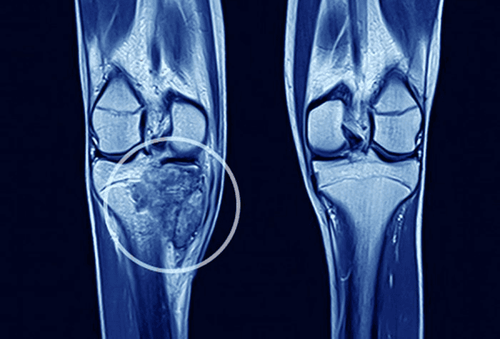

Chủ đề Ung thư thận di căn xương